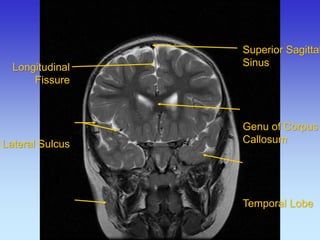

Longitudinal Fissure

Superior Sagittal Sinus

Longitudinal

Fissure

Longitudinal Fissure Lateral Sulcus Superior Sagittal

Sinus

Genu of Corpus

Callosum

Temporal Lobe